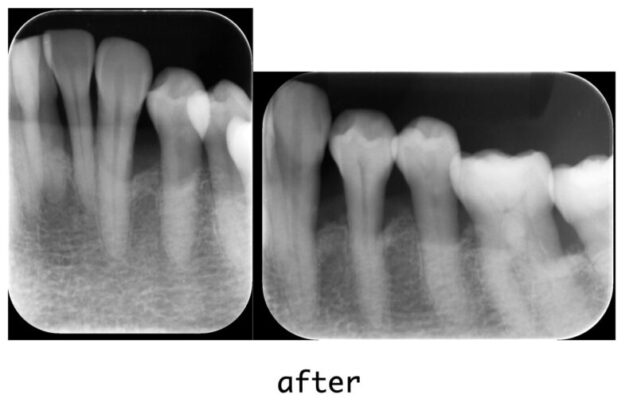

まずは基本治療として5ヶ月間、ブラッシング指導(OHI)を行い、歯石除去(スケーリング)、および歯周ポケット奥深くの汚れを取り除く処置(SRP)を行って、お口の中の炎症を鎮めました。 その後、再評価検査を経て、骨が大きく失われている部位に対して「歯周組織再生療法」を行いました。エムドゲイン(歯周組織再生材料)と骨移植材料を併用し、失われた支持組織の再生を促しました。

現在は治療が完了し、良好な状態を維持するため、3ヶ月に1度のペースで定期的なメインテナンスに通われています。

【院長コメント】 本症例は、私が大学病院に勤務していた時代に執刀・治療を担当したものです。術後15年以上が経過した現在も、定期的なメインテナンスを継続することで、非常に良好な状態を維持されています。適切な治療と継続的なケアによって、重度の歯周病であっても長期的にご自身の歯を保存できる可能性を示す一例です。